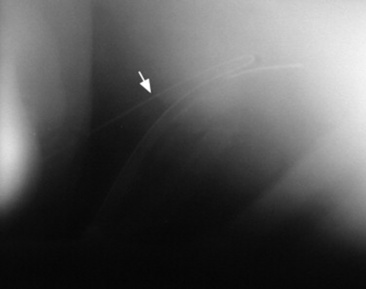

Fig. 30-7 Phonocardiogram and M-mode echocardiogram obtained from a horse with a holodiastolic murmur (DM) caused by aortic valve regurgitation. The M-mode echocardiogram shows diastolic flutter (arrows) of the septal mitral valve leaflet, characteristic of aortic valve insufficiency.

The location of the PMI of the murmur is helpful in distinguishing which valve is involved, although more than one valve can be affected in the same animal. The PMI for lesions of the mitral valve frequently is at the left apex of the heart, although murmurs of mitral regurgitation usually radiate dorsally and toward the left heart base and aortic valve area. Therefore loud systolic murmurs with the PMI in the aortic or mitral valve area in horses are usually mitral regurgitation murmurs. Disorders of the tricuspid valve commonly have the PMI on the right side of the thorax (third to fourth intercostal spaces [horses] or second to third intercostal spaces [cattle]). Infrequently, the murmur may also be heard on the left side of the thorax cranial to the pulmonic valve location in the second intercostal space. Aortic and pulmonic valve lesions produce murmurs with the PMI at the left heart base in the third or fourth intercostal space. Acquired valvular lesions of the mitral and tricuspid valves produce primarily systolic murmurs.72,73,75,80-84 Diastolic tricuspid flow murmurs have been reported, however, and may be associated with right-sided mural or valvular masses in horses85 or may be physiologic, associated with normal blood flow across the atrioventricular valves.86,87 Lesions of the aortic and pulmonic valves may produce diastolic murmurs, systolic murmurs, or both.72,88-90 However, diastolic murmurs of regurgitation are most common in large animals. Aortic regurgitation associated with degenerative valve disease is most common in horses, whereas pulmonic regurgitation associated with bacterial endocarditis is more common in cattle. Aortic valve lesions in horses have primarily holodiastolic, decrescendo, musical murmurs (see Fig. 30-7) but can also be decrescendo, soft, and blowing. Aortic regurgitation murmurs are accompanied by a water-hammer or bounding arterial pulse if the aortic regurgitation is associated with a significant left ventricular volume overload.72,91 The musical quality of the murmur (harmonic) indicates that some part of the aortic valve is vibrating during diastole. The arterial pulse quality becomes more bounding as the aortic regurgitation becomes more severe, and is a good clinical indicator of the degree of left ventricular volume overload. Ventricular premature beats and atrial fibrillation may also be detected in horses with significant aortic regurgitation.